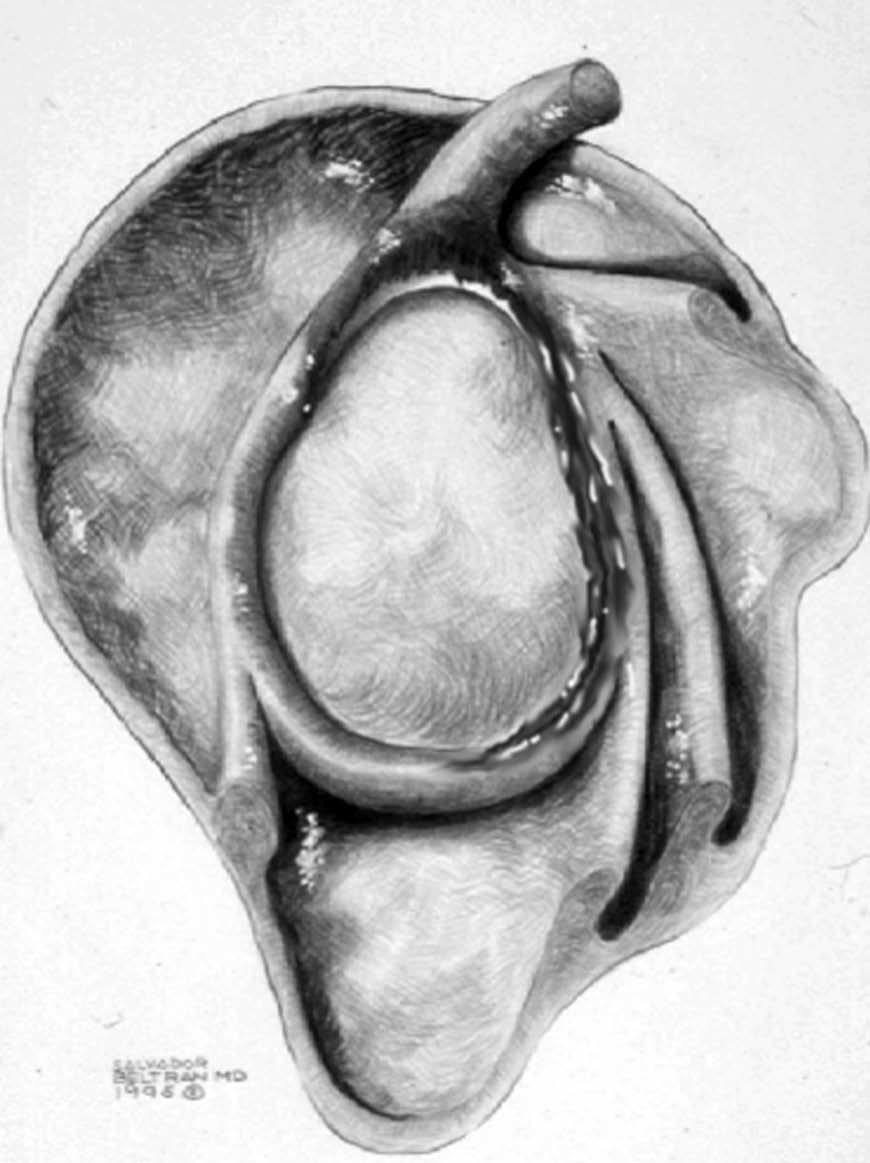

Lesiones del intervalo del manguito de los rotadores

El intervalo del MR es el espacio más o menos triangular localizado entre el borde anterior del tendón del supraespinoso y el borde superior del tendón subescapular. Este espacio anatómico está cubierto por la cápsula articular y contiene las siguientes estructuras (fig. 31): el LGHS, el LCH, el TLB y el borde anterosuperior del borde glenoideo. Los puntos de origen e inserción de estas estructuras se han descrito anteriormente, sin embargo es de notar que la relación entre el TLB y los LGHS y LCH, cambia a medida que estas tres estructuras se extienden desde sus puntos de origen hasta la zona proximal de la corredera bicipital (fig. 6). A nivel medial, aproximadamente a la altura de la articulación glenohumeral, el LCH se encuentra por encima del TLB y el LGHS se encuentra por delante de ambos. A nivel del troquiter el LGHS se coloca por delante y por debajo del TLB. A nivel de la parte proximal de la corredera bicipital, el LGHS se halla por debajo del TLB, mientras que el LCH permanece por encima del TLB. Esta distribución anatómica provee una estabilidad del TLB durante el movimiento del hombro (polea reflectora).